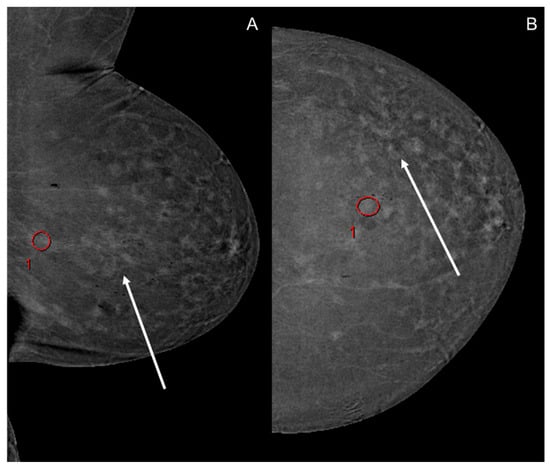

- Meucci, R.; Pistolese, C.A.; Perretta, T.; Vanni, G.; Beninati, E.; Di Tosto, F.; Serio, M.L.; Caliandro, A.; Materazzo, M.; Pellicciaro, M.; et al. Background Parenchymal Enhancement in Contrast-enhanced Spectral Mammography: A Retrospective Analysis and a Pictorial Review of Clinical Cases. In Vivo 2022, 36, 853–858. [Google Scholar] [CrossRef]